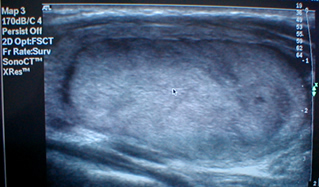

Ultrasound of the thyroid and neck with color Doppler

Ultrasound-guided thyroid puncture with cytological analysis of samples